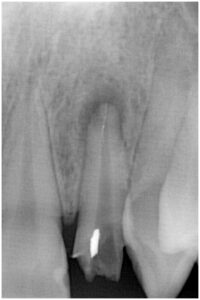

症例1

Before